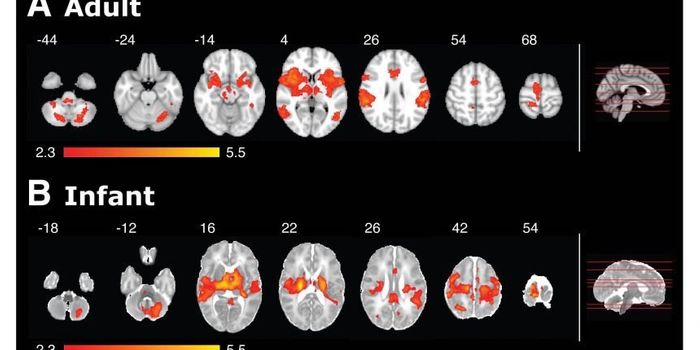

APR 24, 2015NeuroscienceThe study looked at 10 healthy infants aged between one and six days old and 10 healthy adults aged 23-36 years. Infants ...